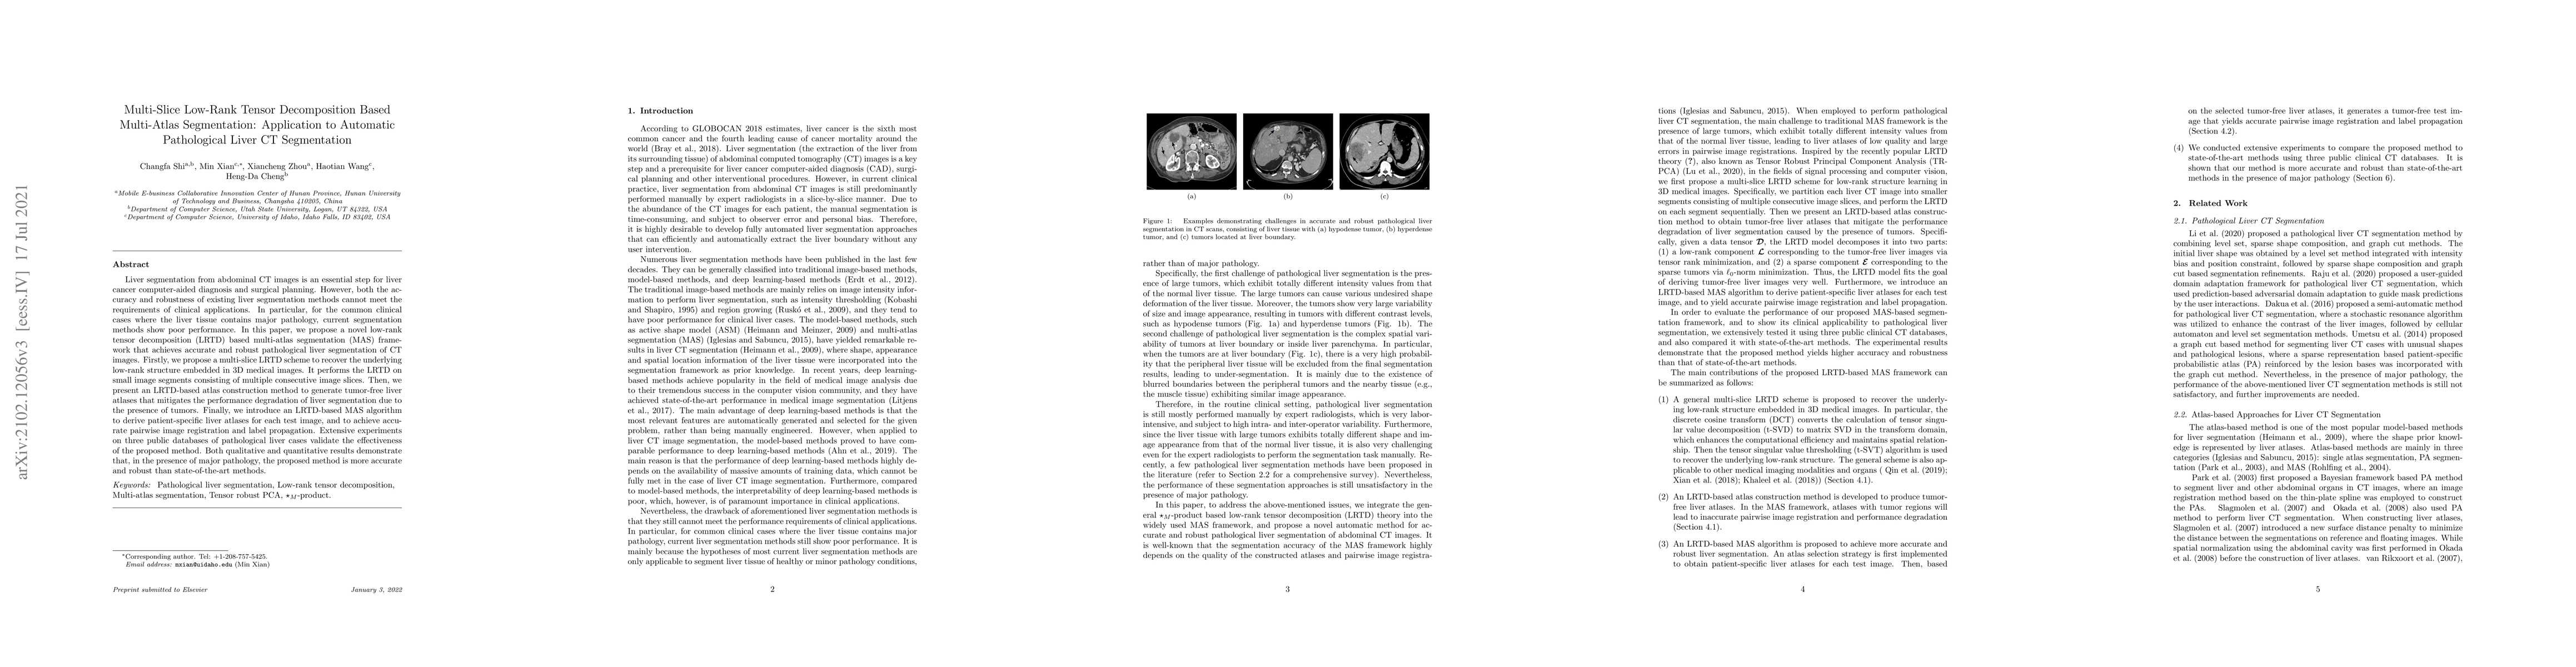

Liver segmentation from abdominal CT images is an essential step for liver cancer computer-aided diagnosis and surgical planning. However, both the accuracy and robustness of existing liver segmentation methods cannot meet the requirements of clinical applications. In particular, for the common clinical cases where the liver tissue contains major pathology, current segmentation methods show poor performance. In this paper, we propose a novel low-rank tensor decomposition (LRTD) based multi-atlas segmentation (MAS) framework that achieves accurate and robust pathological liver segmentation of CT images. Firstly, we propose a multi-slice LRTD scheme to recover the underlying low-rank structure embedded in 3D medical images. It performs the LRTD on small image segments consisting of multiple consecutive image slices. Then, we present an LRTD-based atlas construction method to generate tumor-free liver atlases that mitigates the performance degradation of liver segmentation due to the presence of tumors. Finally, we introduce an LRTD-based MAS algorithm to derive patient-specific liver atlases for each test image, and to achieve accurate pairwise image registration and label propagation. Extensive experiments on three public databases of pathological liver cases validate the effectiveness of the proposed method. Both qualitative and quantitative results demonstrate that, in the presence of major pathology, the proposed method is more accurate and robust than state-of-the-art methods.